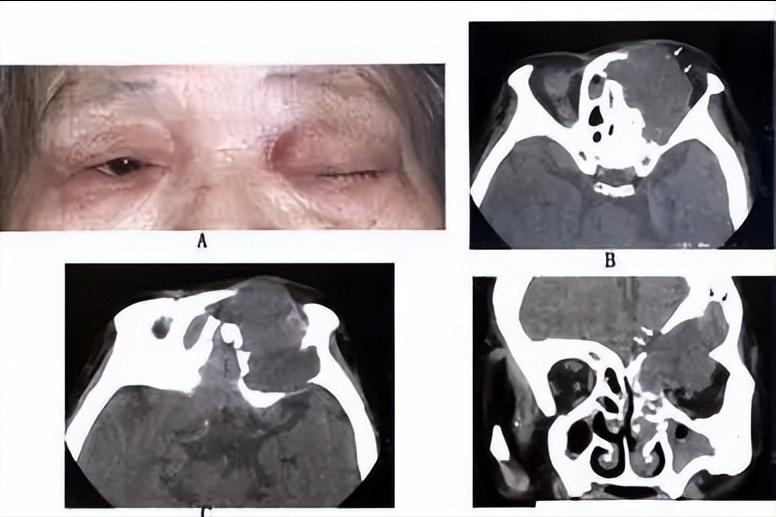

鼻窦黏液囊肿多发生在额窦和筛窦,蝶窦者较少,上颌窦最少,巨大的鼻窦黏液囊肿可侵入眶内和颅内。本病晚期并发感染,可转化为脓囊肿,其破坏性更大,可引起脑膜炎、脑脊液鼻漏或海绵窦血栓等。

鼻窦黏液囊肿的临床表现早期可无任何症状,以后黏液囊肿逐渐增大,压迫囊壁,引起头痛。若突入眶内可使眼球移位,并有复视、流泪、视力障碍等症状。囊肿发生于筛窦者眼球向外移位,发生于额窦者眼球向外下方移位。蝶窦黏液囊肿症状复杂,可致眼球突出,并压迫眶尖而致失明、眼肌麻痹、眼部感觉障碍和疼痛等症状,出现眶尖综合征。囊肿向上发展压迫脑垂体,可引起闭经、性欲减退、尿崩等内分泌失调现象,若压迫颈内动脉可致该动脉发生血栓。若蝶窦黏液囊肿向前壁破溃,黏液排出到鼻腔,以上症状暂时缓解。囊肿除了出现局部症状外还可以出现高热及周身不适等全身症状。

鼻窦黏液囊肿根据症状,鼻镜检查和影像学检查,囊肿穿刺等可诊断。